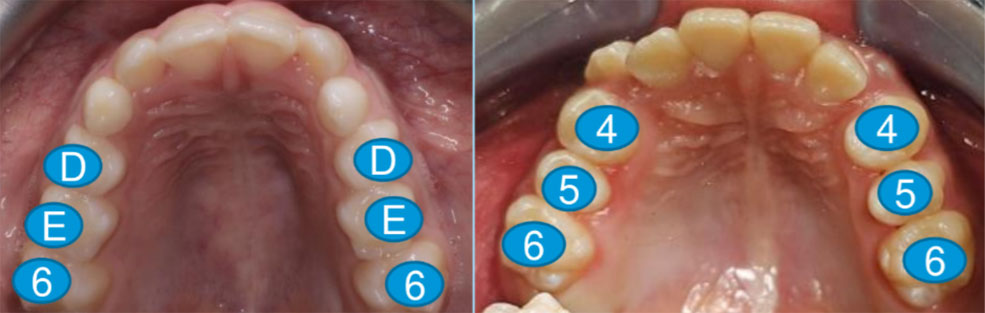

Um planejamento mais refinado envolve análise detalhada da face, da oclusão, das estruturas ósseas e dos hábitos do paciente.

Recursos como escaneamento intraoral, tomografia (CBCT) e escaneamento facial permitem uma avaliação tridimensional completa.

Enquanto um tratamento comum pode se basear apenas no modelo digital dos dentes, um tratamento de excelência considera os hábitos e saúde geral do paciente, seus limites biológicos e o impacto estético global, reduzindo riscos e aumentando a previsibilidade.